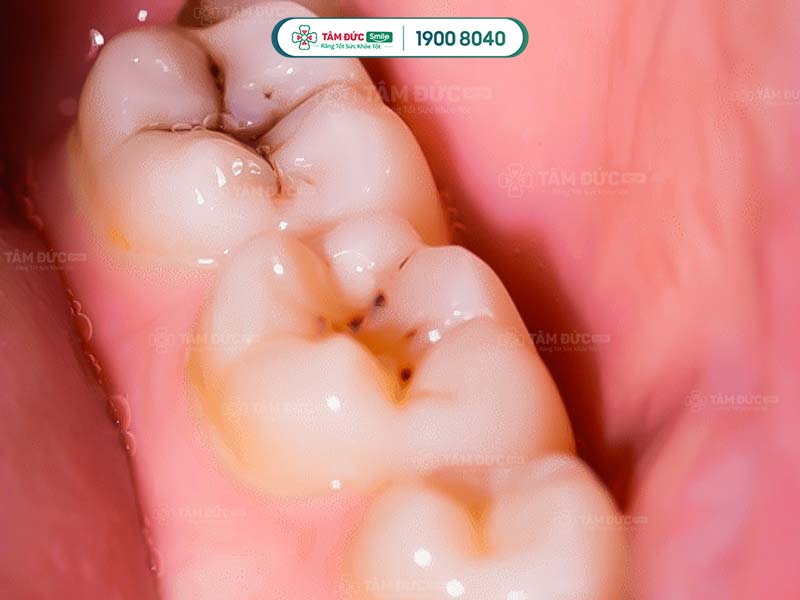

1.1. Bề mặt răng có các đốm nâu đen

Đây là dấu hiệu điển hình nhất khi răng khôn bị sâu. Các đốm nâu đen này xuất hiện do vi khuẩn sâu răng tấn công và ăn mòn men răng, gây sâu răng.

Răng khôn có hình thể và bề mặt lớn hơn các răng khác. Mặt nhai của răng khôn có nhiều rãnh nhỏ, là nơi lý tưởng để vi khuẩn tích tụ và phát triển.